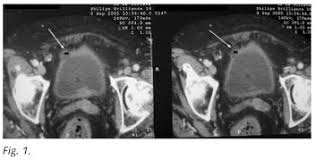

Para la cistitis no existe un gran avance en lo que se refiere a terapia génica pero existe una complicacion denominada cistitis enfisematosa (CE) es una rara complicación en el curso de una infección del tracto urinario inferior producto de patógenos productores de gas. Se caracteriza por la presencia de aire dentro de la pared y el lumen de la vejiga y por afectar clásicamente a mujeres diabéticas de edad media.